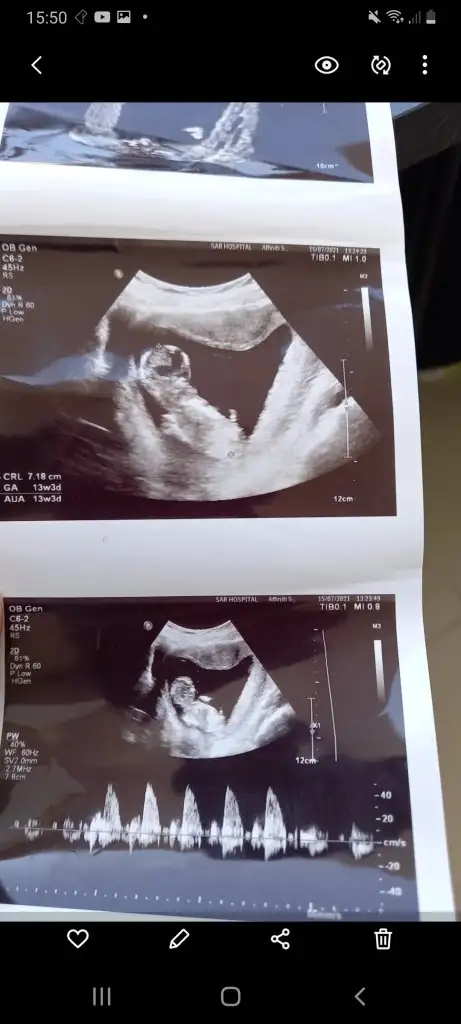

Bir de 16 haftalık ultrasona bakar mısın lütfenYüzde yüz milyon erkek besbelli canım benim oğlumun da böyleydi ultrason görüntüleri

Geç oldu kusura bakmayın oğlumun 11 haftalık ultrason resmi burda cinsiyetini ben doktora söylemiştim erkek değil mi diyeOlur teşekkürler